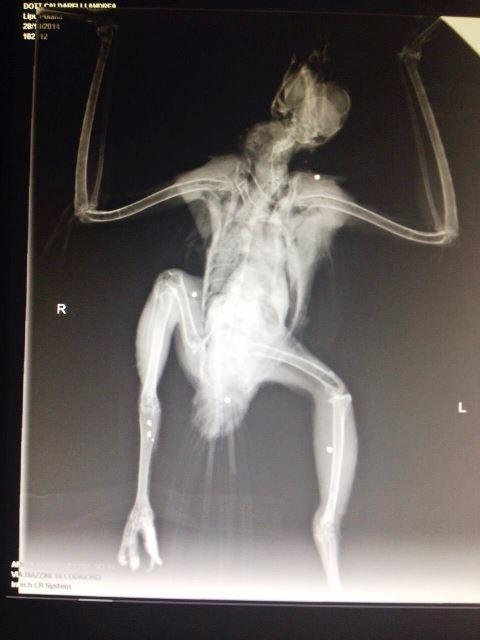

Un esemplare di Poiana-Buteo buteo ferito da colpi di fucile

"Ennesimo criminale atto di bracconaggio". Così il presidente della Lipu Ferrara Borghi commenta quanto accaduto a Porto Tolle, dove un esemplare di poiana è stato colpito da diverse pallottole. L'animale è stato portato dall’Assoc. Lida, al Centro di Recupero della Lipu Giardino delle Capinere a Ferrara, in un primo momento era stato consegnato alla Forestale di Bosco Mesola, da un signore che l’aveva raccolto nella zona di Porto Tolle (RO), dopo aver visto delle persone sparargli. Il fatto è stato confermato dalle radiografie effettuate dal Dr. Caldarelli, che evidenziano la presenza di pallini di piombo in vari punti del corpo, ed ha effettuato un primo intervento per la riduzione della frattura sulla zampa destra, sperando che non siano state colpite parti interne su cui è molto più difficile intervenire. "E' senza alcun dubbio un atto vandalico consapevole, in quanto è impossibile anche per il più sprovveduto delle persone che girano con un fucile, confonderla con una specie cacciabile".